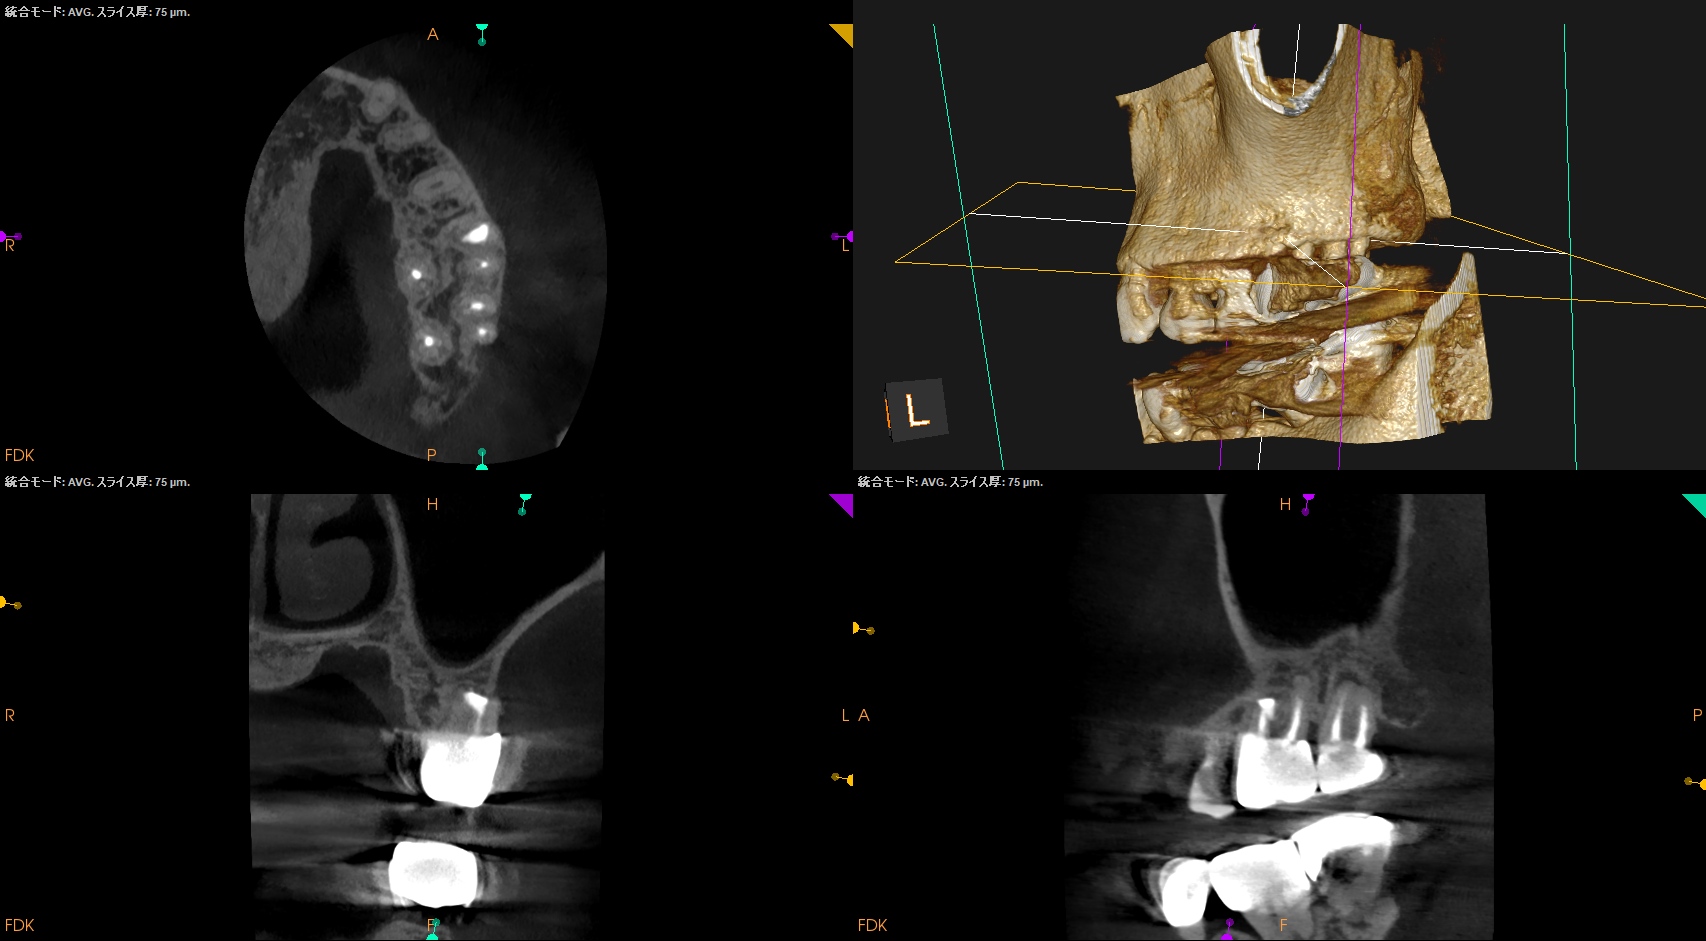

昨日の治療の1年後の予後である。

Retroprepで穿孔させてしまい、即日Retrofill(穿孔封鎖)した#14は治癒しただろうか?

Post-op 1yr recall(2026.4.15)

1年前と比較した。

臨床症状、骨欠損も完治したのでこの日で終診とさせていただいた。